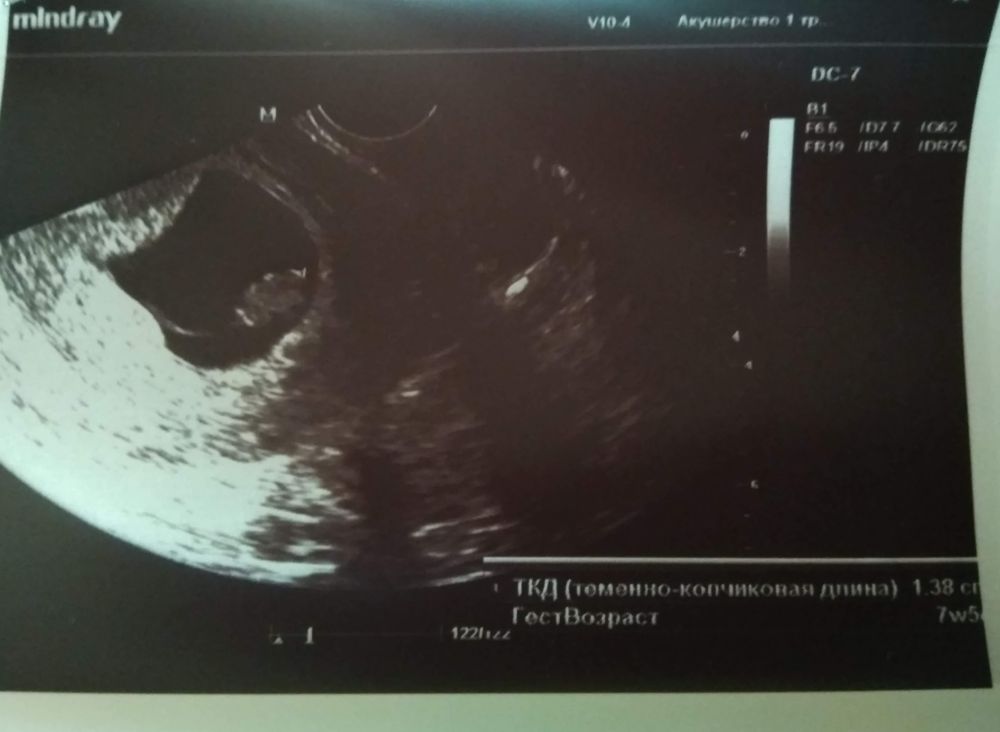

8+1 недель УЗИ

Изображение Kate Agaeva, вот нашла, 13.8 мм. Сказала начали появляться зачатки ручек и ножек) Зачатки, а ваша узистка уже прям человечка хотела увидеть🤦🏻‍♀️ Так что все хорошо у Вас), не переживайте

Да не сильно отстает! У меня когда ктр 13 мм был мне срок по узи поставили 7+5 . Не переживайте! Все хорошо! Малыш ваш красавчик! Догонит и перегонит всех🥰

Аня Жеребьёва, ну так и поставили.. а если считать по переносу или месячным он больше